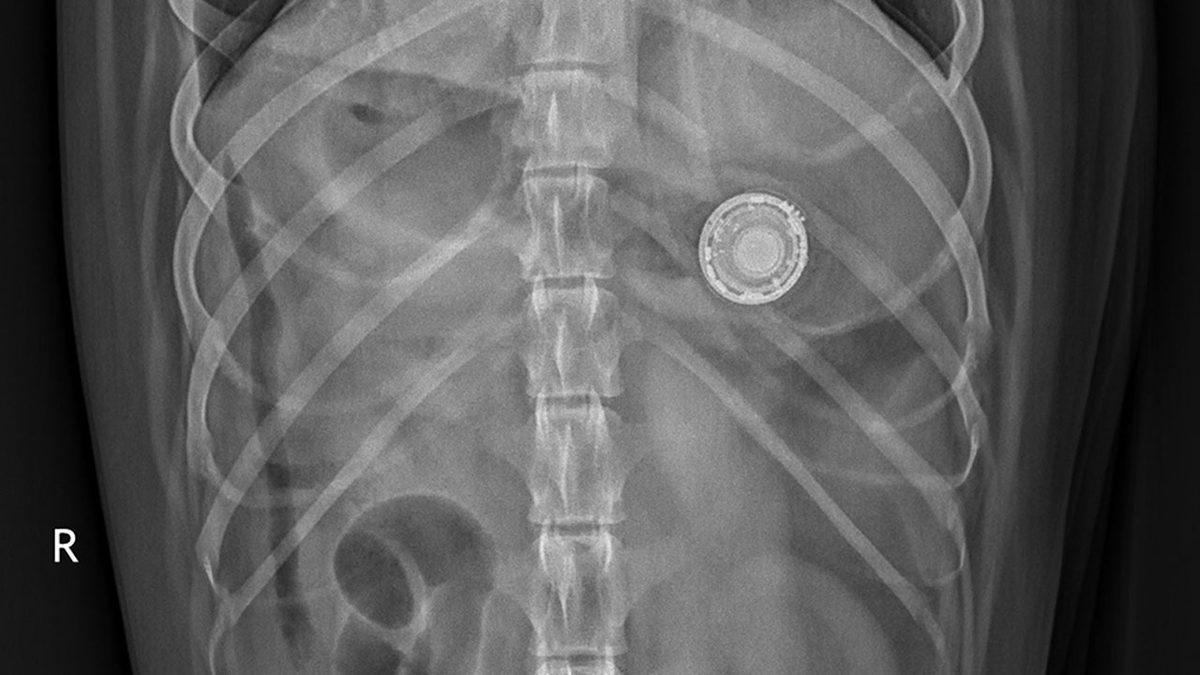

*AirTag yutan bir köpeğin röntgen görüntüsü.

AirTag'ın çapı, sadece 3,2 santimetre. Bu durum, bir köpeğin AirTag yutması durumunda, cihazın sindirim sistemini rahatlıkla geçebileceği anlamına geliyor. Diyelim ki köpeğiniz bir AirTag yuttu, kusma veya dışkı yoluyla ürün kendi kendine çıkabilir. Ancak buradaki esas mesele, AirTag'ın çiğnenmesi durumunda yaşanabilecekler. Çok da dayanıklı bir ürün olmayan AirTag'ın çiğnenmesi, içindeki pilin sızıntı yapmasına yol açabilir. İşte bu da köpeğinizin zehirlenmesine ve hatta hayatını kaybetmesine yol açabilir.